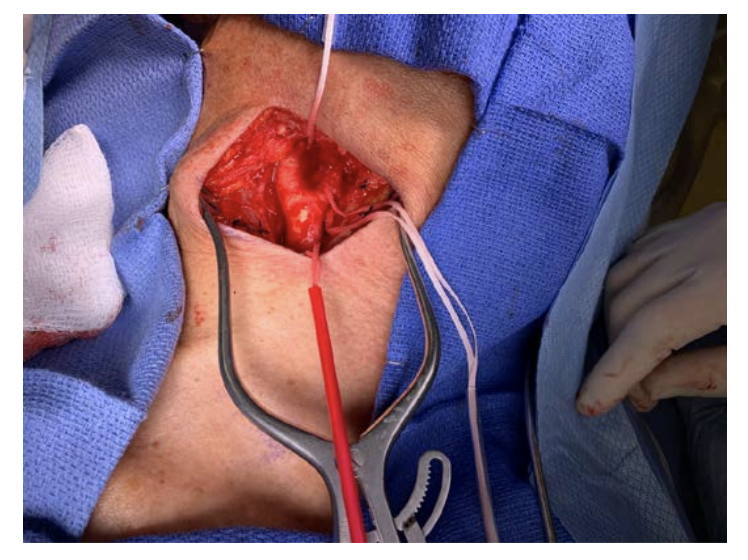

A carotid endarterectomy was performed on April 8th, 2 months after the patient’s stroke and 1 month after he had documented recovery from his COVID-19 illness. A standard operating approach was planned with a dedicated, experienced vascular surgery operating room team. Particular attention was paid to personal protective equipment (PPE) and procedures. The procedure was performed in an operating room that was equipped with a separate air-circulation machine (HEPA filter) for airborne/droplet isolation, in addition to the negative pressure setting. Surgical attire was upgraded to full PPE with modified Stryker orthopedic hoods (toga gown) ventilated suits and N95 masks (Figure 4). The operation was performed under modified general anesthesia with carotid shunting and possible patching if needed. General anesthesia was induced with fentanyl, lidocaine, propofol, and succinylcholine. Mask ventilation was not attempted in order to minimize spreading aerosols. Oral intubation was performed using video laryngoscopy to avoid excessive airway manipulation. With dissection and exposure of the carotid bifurcation (Figure 5), it was apparent that the patient had significant inflammation of the carotid artery. We anticoagulated with a larger dose of intravenous heparin. Upon opening the carotid bifurcation, a soft, friable plaque was encountered (Figure 6, Video 1). Microscopic examination of the plaque revealed fibrocalcific change with predominantly blood, fibrin, and focal acute and chronic inflammation. Definitive vasculitis, microorganisms, and viral inclusions were not identified (Figure 7).

The distal internal carotid artery was large and accommodated an intraluminal shunt. Endarterectomy was performed in standard fashion; however, due to the perivascular inflammation, the residual carotid wall was thin and friable. There was no distal intimal flap and tacking sutures were not needed. The vessel was closed primarily, without a patch, because of concern for foreign-body infection. Final gross pathology revealed a pink-yellow tan, hemorrhagic, and calcified cut surface with further special staining pending.

Upon the dissection of the carotid artery, we realized the abnormally inflamed characteristics of the vessel and the low bifurcation. We carefully identified the adhered vagus and hypoglossal nerves in addition to large lymph nodes over the bifurcation. We elected to shunt per our routine approach.22-28 After the plaque was safely removed, we elected to avoid a patch and do a primary closure in the face of possible future infection of any foreign material.29-33 Two main observations emerged during the operation:

1. The amount of perivascular inflammation required extra care in dissection and resulted in the thinnest of endarterectomized carotid wall. Fortunately, we were able to do primary closure. Changes to the carotid artery or vascular plaques during COVID-19 are not fully understood. At the cellular level, the coronavirus uses the angiotensin-converting enzyme 2 (ACE2) receptor and TMPRSS2 protease to enter into host cells and proliferate. Activation of ACE2 receptors, which are widely expressed, and TMPRSS2 proteases in endothelial and smooth muscle cells of the vasculature, is thought to be involved in triggering the diffuse endothelial inflammation, vasculitis, thrombosis, and microangiopathy of vascularized tissues seen in COVID-19 patients.34,35 Endothelial dysfunction associated with cell death, injury, and inflammation can result from the recruitment of immune cells, leading to vascular derangements and increased atherosclerotic risk.35,36 Widespread endothelial dysfunction results in vasoconstriction, ischemia, inflammation, and a procoagulant state.36 We were reluctant to use an autogenous vein, since the presence of its endothelial and smooth muscle cells would make it prone to possible inflammation and thrombosis in COVID-19.

2. The fragile nature of the pedunculated lesion could have embolized during the procedure, dissection and/or mobilization of the plaque. Gentle, minimal manipulation of the carotid bifurcation was required. We placed the distal clamp first, ensured that we were past the lesion, and then placed the shunt.